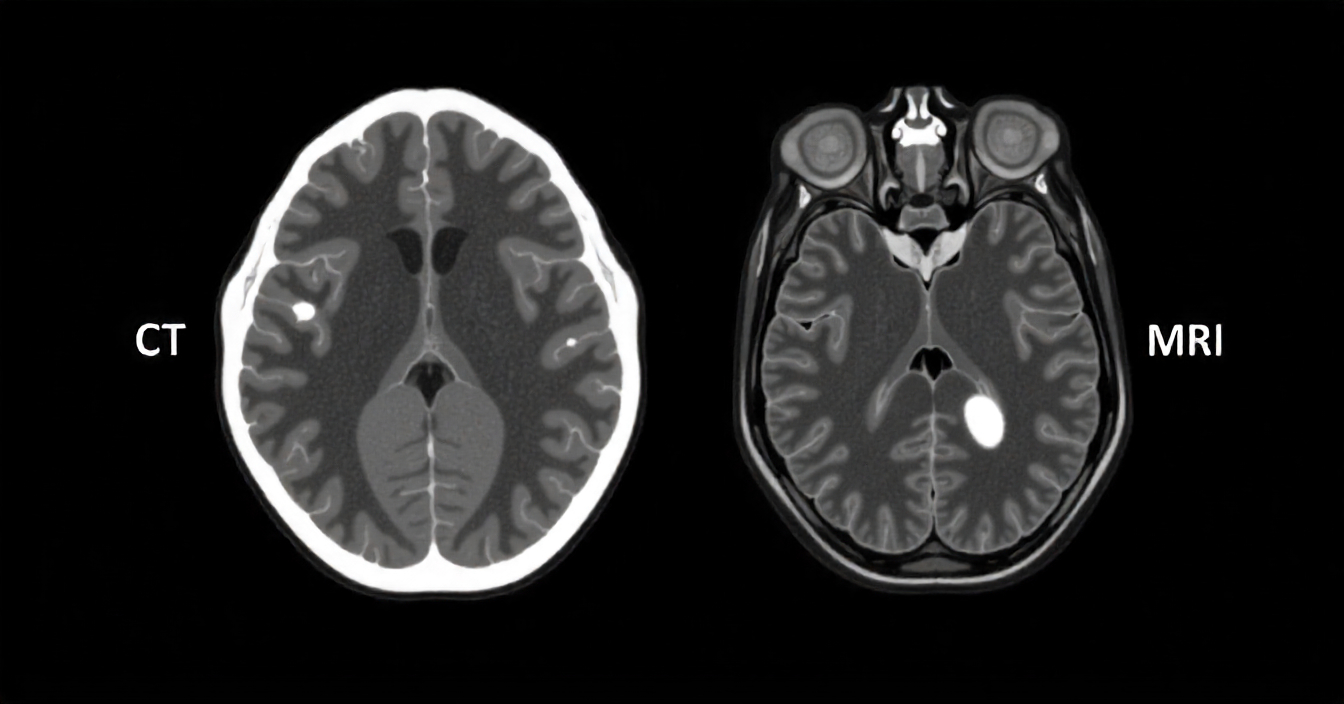

CT koroner dan MRI jantung sama-sama penting, namun bertujuan berbeda. CT koroner sangat baik untuk memvisualisasi anatomi arteri koroner dan menyingkirkan penyempitan signifikan pada pasien risiko rendah–menengah. MRI jantung (CMR) unggul untuk menilai fungsi pompa, jaringan parut (late gadolinium enhancement), edema, viabilitas miokard, dan berbagai kardiomiopati. Memahami perbedaan ini membantu dokter menentukan tes paling efisien, sering kali dikombinasikan dengan echo, EKG/Holter, atau angiogram sesuai kebutuhan.

Ringkasan Perbedaan CT Koroner vs MRI Jantung

CT Koroner (Cardiac CT / CCTA)

• Tujuan utama: melihat anatomi arteri koroner, plak, dan derajat stenosis.

• Kekuatan: sangat baik untuk rule-out penyakit arteri koroner bermakna pada risiko rendah–menengah.

• Keterbatasan: paparan radiasi & penggunaan kontras iodin; stenosis borderline kadang perlu konfirmasi fungsional/angiogram.

• Tambahan: skor kalsium (CAC) untuk stratifikasi risiko, FFR-CT di pusat tertentu.

MRI Jantung (Cardiac MRI / CMR)

• Tujuan utama: menilai fungsi ventrikel, viabilitas, jaringan parut/edema, miokarditis, kardiomiopati.

• Kekuatan: karakterisasi jaringan sangat detail; tanpa radiasi.

• Keterbatasan: durasi lebih lama, sensitif terhadap arrhythmia/motion, tidak ideal untuk detail lumen koroner kecil.

• Kontras: gadolinium (perlu perhatian pada gangguan ginjal berat).